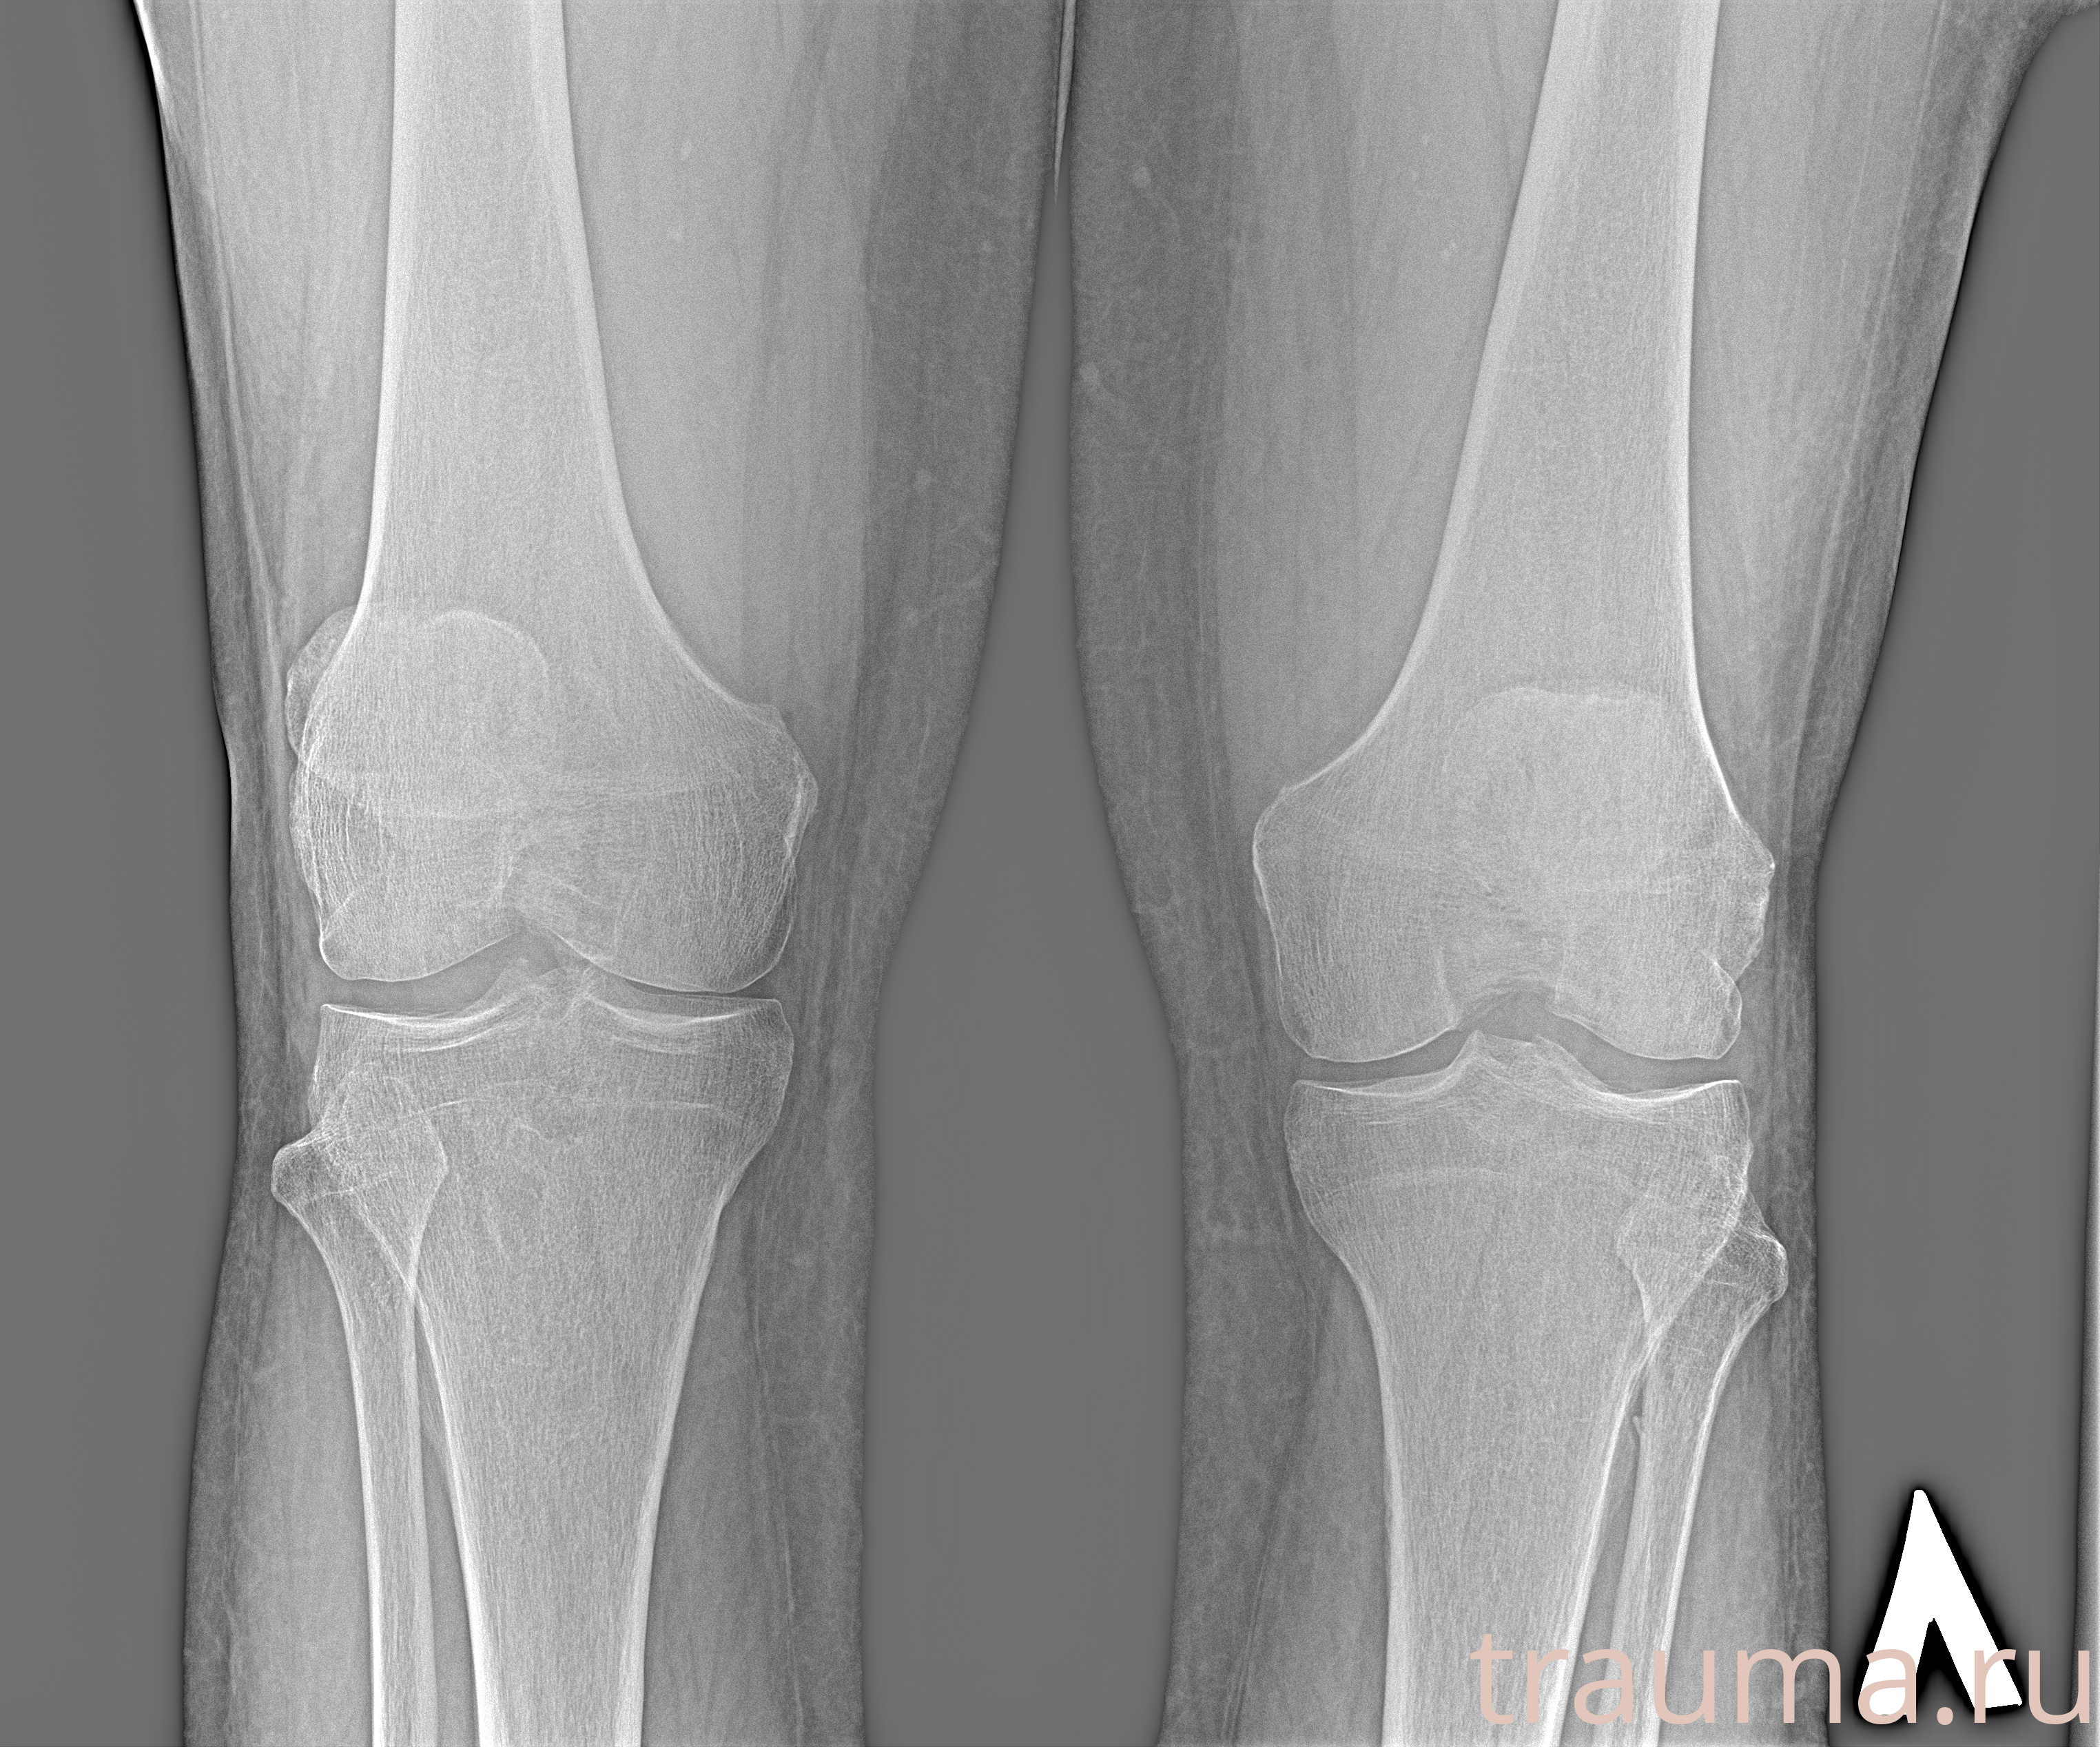

Рентгенограммы

Рентген на дому: по вашему адресу приезжает врач-рентгенолог, травматолог-ортопед с мобильным рентгеновским аппаратом, проводит диагностику травмы или заболевания, делает необходимые рентгенограммы, дает рекомендации по дальнейшему лечению. Получить качественные снимки в домашних условиях возможно благодаря уникальной методике, разработанной МосРентген Центром для института  Склифосовского